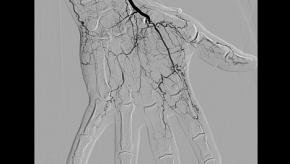

Cannabis Arteritis

Following the November elections, there are now 29 states and the District of Columbia that have legalized marijuana (aka cannabis) for medical use. Of these, eight states and the District of Columbia have also approved laws legalizing marijuana for recreational use. Regardless of the stated benefits associated with marijuana use, there are potential health risks. One of these which rheumatologists may see more of in the future is cannabis arteritis. The following is a recent case we saw at the University of Colorado.